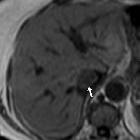

Isolated

intracaval recurrence of resected renal carcinoma. Dynamic contrast-enhanced MRI acquisition showed strong enhancement in the tumour thrombus (arrows) in the arterial phase (f), portal phase (g) and delayed phase (h).